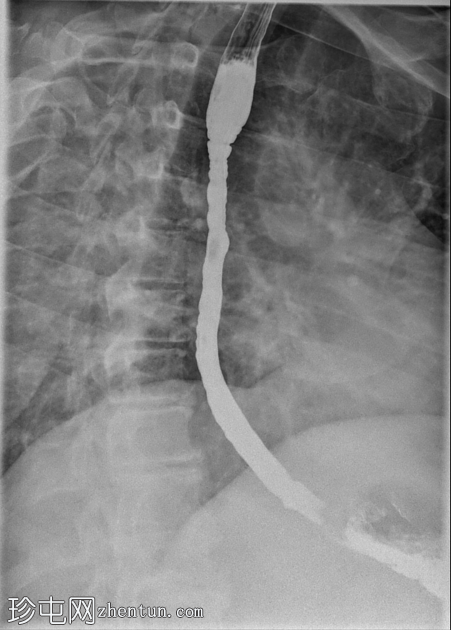

3.png

矢状位

透视食管造影显示食管内可见同心环状轻度狭窄,符合嗜酸性食管炎的影像学表现。近端食管轻度扩张,提示存在固定性狭窄。未见肿块或食管裂孔疝。

钡餐食管造影通常显示固定的同心环(“气管化”)、节段性狭窄或食管管径变细。